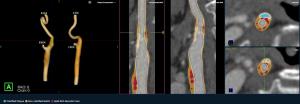

Emerging AI Software for CT Plaque Analysis ‘Revolutionizes’ Carotid Artery Assessment